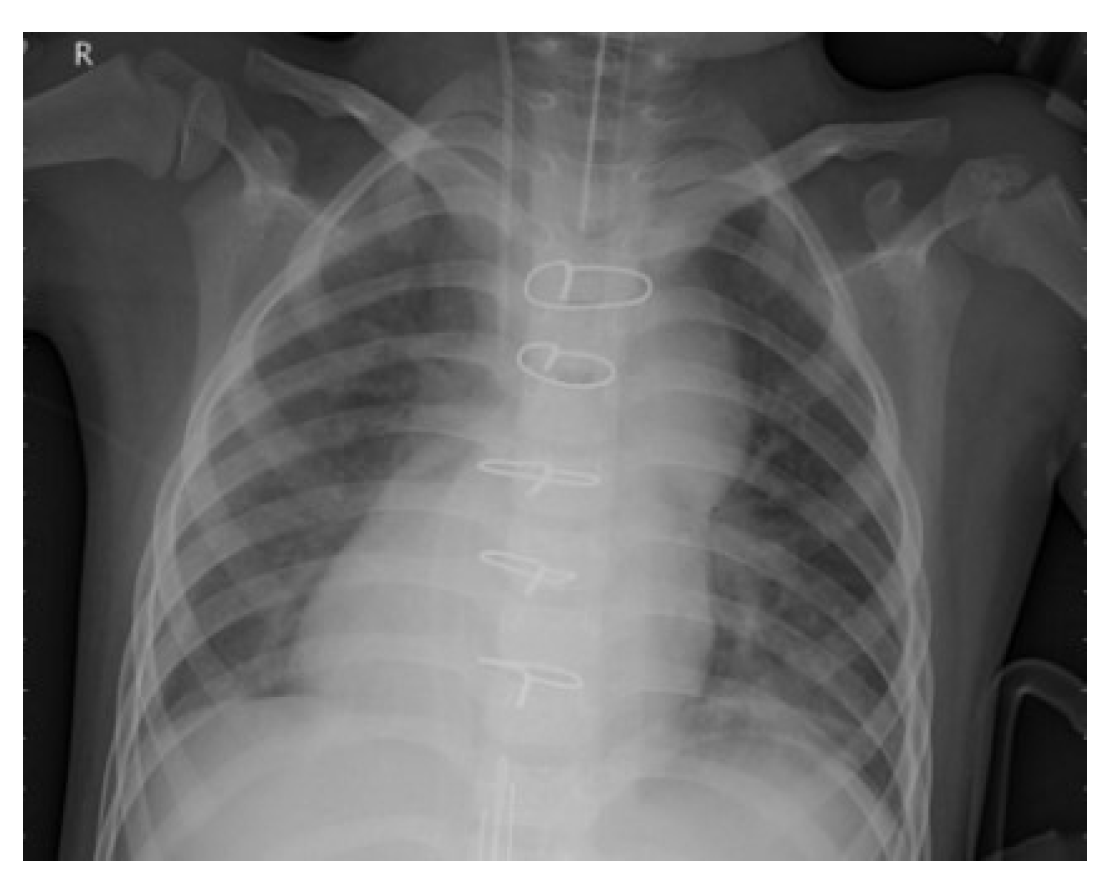

To improve the authenticity of the research, this paper selected a large number of athletes from professional sports colleges. X-ray images of the above athletes’ lungs were collected. There were 2806 men and 2806 women, totaling 5612, accounting for 30% of the unit athletes in 2020. The ages were between 18 and 25 years old. The shortest training period was only 1 year and the longest training period was 5 years. Figure 6 and Figure 7 are the medical images of the part collected.

A total of 5612 original grayscale images were collected and randomly clipped to 224 × 224 grayscale images, with the pixel value divided by 255 to normalize the data, thereby accelerating the training process. Finally, the data were divided into a training set, a validation set and a test set at a 8:1:1 ratio, which is convenient for the training and evaluation of subsequent models.

Figure 7. Lung image with pneumonia.